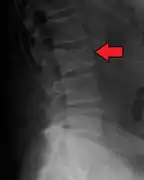

Bone pain

Illustration showing the most common site of bone lesions in vertebrae

Bone pain affects almost 70% of people with multiple myeloma and is one of the most common symptoms.[2]:653[22] Myeloma bone pain usually involves the spine and ribs, and worsens with activity. Persistent, localized pain may indicate a pathological bone fracture. Involvement of the vertebrae may lead to spinal cord compression or kyphosis. Myeloma bone disease is due to the overexpression of receptor activator for nuclear factor κ B ligand (RANKL) by bone marrow stroma. RANKL activates osteoclasts, which resorb bone. The resultant bone lesions are lytic (cause breakdown) in nature, and are best seen in plain radiographs, which may show "punched-out" resorptive lesions (including the "raindrop" appearance of the skull on radiography). The breakdown of bone also leads to the release of calcium ions into the blood, leading to hypercalcemia and its associated symptoms.[23]